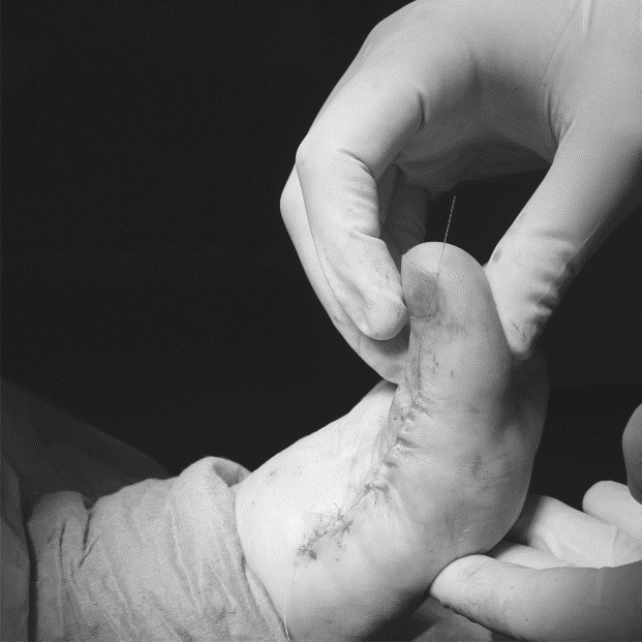

Resultados de Implante completo en paciente con Hallux Rigidux